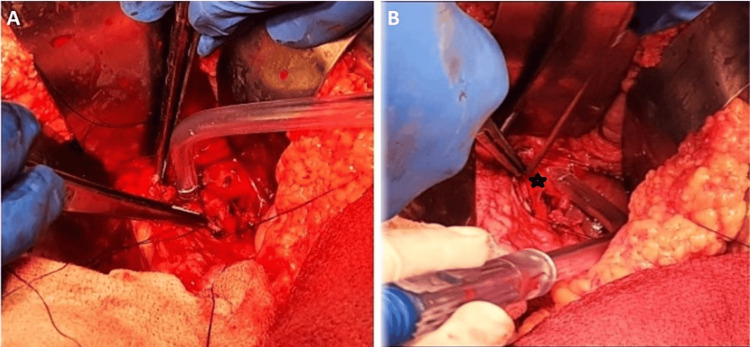

Faced with these clinical and radiological findings and the unavailability of interventional radiologists in our structure, the decision was to proceed with an emergency laparotomy. The patient underwent an upper median laparotomy, and we found stigmata of previous bleeding covering the hepaticojejunostomy with active bleeding around the common hepatic artery (Figure 2A, 2B). GDA pseudoaneurysm was confirmed, and we performed a careful dissection of the GDA with ligation of the inflow and outflow and the resection of the aneurysm.